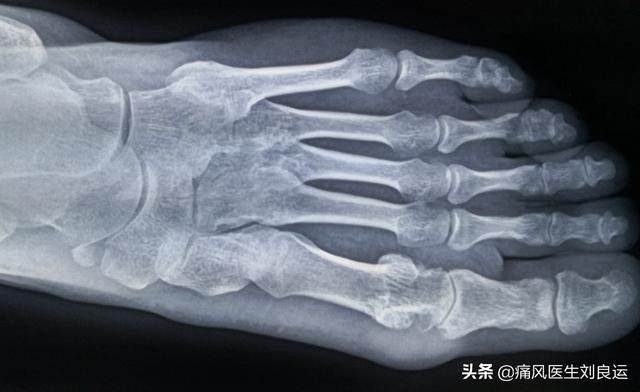

L'arthrite goutteuse aiguë typique se manifeste généralement de manière monoarticulaire, 70 % des premières crises étant localisées dans la première articulation métatarso-phalangienne, suivie des articulations métatarso-phalangiennes, de la cheville, des doigts et du poignet, et, en cas de récidive, des articulations du genou et du coude.

Les douleurs articulaires de l'arthrite goutteuse aiguë sont principalement dues à la précipitation de l'acide urique indissoluble dans le sang pour former des sels cristallins dans les articulations, le cartilage, la synoviale, etc. Lorsque les cristaux d'urate s'accumulent dans une certaine mesure, s'ils tombent en raison d'une hausse ou d'une baisse soudaine de l'acide urique, ils provoquent une réponse immunitaire dans les cellules immunitaires du sang, libérant des substances inflammatoires et conduisant à l'inflammation.

Comme nous le savons, l'apparition de la goutte est due au fait que le taux d'acide urique de l'organisme dépasse depuis longtemps la norme, l'acide urique dans le sang ne peut pas être entièrement dissous, ce qui entraîne la formation de cristaux d'urate, qui se déposent dans les articulations et dans d'autres parties du corps. Lorsque la concentration locale de cristaux d'urate est trop élevée, le système immunitaire de l'organisme est "alerté" et élimine ces "mauvaises choses" indésirables, ce qui provoque de fortes douleurs locales, Lorsque le système immunitaire est "alerté" pour éliminer ces "mauvaises choses", il en résulte une douleur locale intense, une rougeur, un gonflement et d'autres réactions inflammatoires, ainsi que les symptômes d'une crise de goutte. On peut dire que le niveau de concentration d'acide urique dans notre corps est la cause la plus importante des crises de goutte. La récurrence des crises de goutte est due aux changements fréquents et radicaux de la concentration d'acide urique.

La goutte est une arthropathie associée à des cristaux, causée par le dépôt de cristaux d'urate monosodique, qui se produit lorsque le taux d'acide urique dans le sang dépasse le niveau de saturation et que les cristaux précipitent et se déposent dans les articulations et d'autres tissus. La raison pour laquelle la goutte est difficile à guérir est qu'une fois les cristaux d'acide urique formés, il est difficile de les dissoudre et de les évacuer complètement, et qu'une fois sous l'action de facteurs déclenchants, ils peuvent à nouveau provoquer des crises de goutte.

La raison pour laquelle la goutte est si difficile à guérir n'est pas du tout surprenante si l'on examine les causes de la goutte. La cause première de la goutte, ou les effets à long terme d'un taux élevé d'acide urique, le taux d'acide urique dans le sang est élevé pendant une longue période, la solubilité de l'urate est faible, ce qui entraîne la précipitation de minuscules cristaux d'urate dans le sang, ces cristaux d'urate voyagent avec le sang dans tout le corps, la formation la plus probable étant le dépôt dans les articulations des membres inférieurs, le dépôt de sel d'acide urique, s'il est déclenché par la réponse immunitaire du corps, causé par la rougeur, le gonflement, la douleur et d'autres aspects de la réponse inflammatoire, nous l'appelons généralement une crise de goutte aiguë. Nous parlons généralement d'une crise de goutte aiguë. Le problème de l'hyperacidité urique fait partie des problèmes métaboliques chroniques de l'organisme, principalement dus au fait que le métabolisme de l'acide urique a un problème, que la production d'acide urique est plus importante et que l'excrétion de l'acide urique est insuffisante en raison de la diminution de la capacité d'excrétion du métabolisme de l'acide urique, que la grande majorité des cas sont irréversibles et que, par conséquent, la goutte est souvent incapable de guérir complètement le problème.

Les amis qui ont eu une crise de goutte savent que la raison pour laquelle on l'appelle "goutte" est que la maladie va et vient sans laisser de trace, tout comme le vent, lorsqu'il arrive rapidement, après un certain temps, la douleur s'estompe souvent complètement, pour devenir la crise de goutte aiguë après la période intermittente. Bien qu'un taux élevé d'acide urique soit la cause principale de la goutte, le traitement de la crise aiguë de goutte reste généralement un traitement anti-inflammatoire et analgésique, et lorsque la goutte ne fait plus mal, cela ne signifie pas que la goutte est guérie, mais que la réaction inflammatoire causée par un taux élevé d'acide urique a seulement été réduite. Des études ont montré que pour éviter efficacement les crises de goutte, la valeur de l'acide urique doit être contrôlée à au moins 360 μmol/L ou moins pendant l'intervalle de goutte, et pour le diagnostic des calculs goutteux, ou des crises de goutte multiples et récurrentes, il est encore plus important de contrôler strictement le niveau d'acide urique, et il est encore mieux de contrôler cette valeur à moins de 300, et contrôler le niveau d'acide urique à moins de 300 et le maintenir sous un contrôle régulier non seulement réduit efficacement les crises de goutte, mais aide également à la dépressurisation et à l'amélioration de la qualité de vie. La raison en est en fait très simple, la concentration d'acide urique dans le sang est abaissée, le dépôt d'urate sera redissous dans la circulation sanguine, pour donner un exemple pas trop approprié, comme une petite quantité d'eau, une grande quantité de sel, le sel coulera au fond de l'eau, et si vous ajoutez un peu plus d'eau, lentement le sel se dissoudra, contrôlez le bon ! Il en va de même pour les niveaux d'acide urique, qui doivent se situer dans une certaine fourchette afin que les calculs de la goutte se dissolvent lentement.